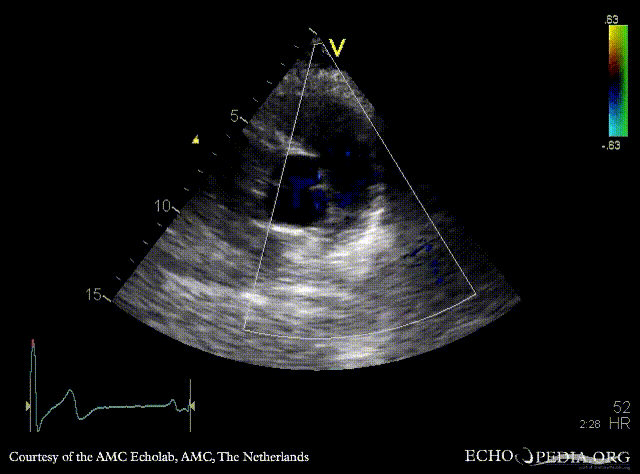

Severe pulmonary regurgitation

E00380.gif